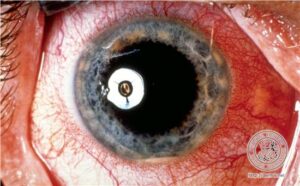

Aphthosis Behcet s DiseaseBehcet’s disease is a symptom complex of oral and genital ulceration and iritis that has a worldwide distribution but is most common in the Pacific rim and eastern Mediterranean . The presence of oral ulceration plus any two signs of genital ulceration, skin lesions (e.g., pustules or nodules), or eye lesions (e.g., uveitis or retinal vasculitis) is diagnostic. |

The extracutaneous manifestations are categorized as oral and/or genital aphthae; vasculo-, ocular-, entero-, or neuro-Behcet’s disease; renal disease; and arthritis. Oral apthosis recurring at least three times over a 12-month period is essential to the diagnosis (. In vasculo-Behcet’s disease, aneurysms and occlusive venous and arterial main vessel lesions occur. The ocular manifestations include uveitis, hypopyon iritis, optic neuritis, and choroiditis. Entero-Behcet’s disease manifests as diarrhea, constipation, abdominal pain, vomiting, and melena. Neuro-Behcet’s disease presents as brainstem dysfunction, meningoencephalitis, organic psychiatric symptoms, and mononeuritis multiplex . Asymptomatic microhematuria and/or proteinuria are among the renal manifestations. An oligoarthritis may involve the wrist, elbow, knee, or ankle joints. Morbidity and mortality in one large series of Turkish patients were greatest in young males; both the onset and the severity of ocular disease were greatest early in the course of disease, suggesting that the “disease burden” in Behcet’s disease is greatest early and that it tends to “burn out” over time .However, neurologic and major vessel disease can occur at any time and can have late onset 5 to 10 years into the course of illness . |

neutrophilic infiltrate with necrosis of the epithelium and connective tissue pathergy of the submucosa and peripherally a border showing dense lymphocytic infiltration with lymphocytic exocytosis and degenerative epithelial changes. Genital aphthae have the same appearance. The large-vessel arteriopathy represents an ischemic sequelum of a mononuclear cell vasculitis of the vasa vasorum (108), whereas venous thrombosis may be due in part to an underlying hypercoagulable state. A lymphocytic vascular reaction with or without mural and intraluminal fibrin deposition is the histopathology of neuro-, entero-, ocular-, and arthritic Behcet’s disease, with other organ changes such as demyelination and intestinal ulceration reflecting resultant ischemia (. The renal histopathology includes IgA nephropathy, focal and diffuse proliferative glomerulonephritis, and amyloidosis . |